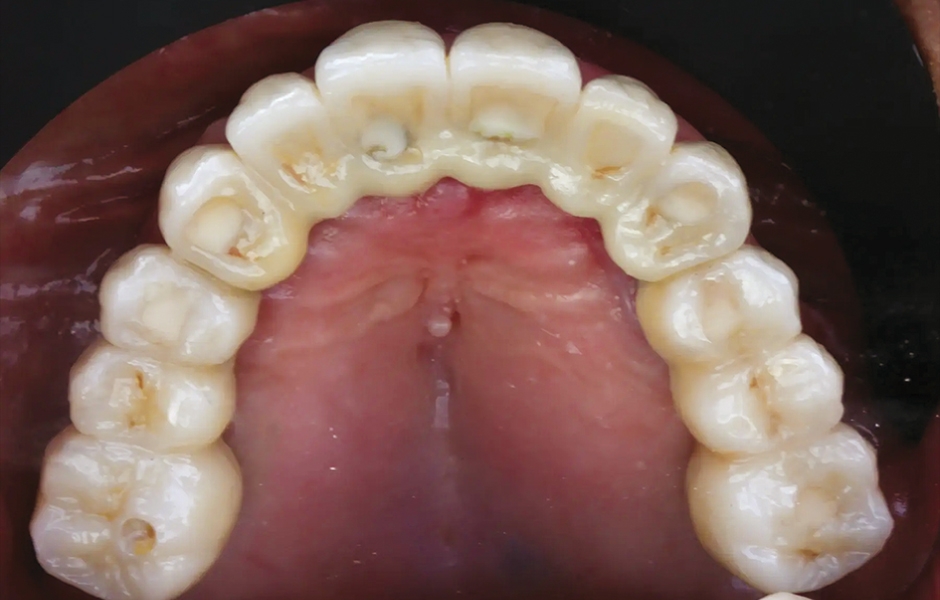

85letý částečně bezzubý pacient byl odeslán na naši kliniku k celkové rehabilitaci horní čelisti. Pacient byl v dobrém celkovém zdravotním stavu a nekuřák. Jeho hlavní stížnosti zahrnovaly obtíže při žvýkání, bolest v horní čelisti a občasný zápach z úst. Klinické a radiologické vyšetření odhalilo krátký fixní metalokeramický můstek nesený sedmi frontálními zuby horní čelisti. Protetická práce se uvolnila a čtyři z pilířových zubů byly strukturálně narušeny. Zbývající tři vykazovaly různé stupně kazivých lézí a parodontálních problémů. Byla stanovena diagnóza selhávající dentice (obr. 1 a 2).

Obr. 1: Výchozí situace, čelní pohled. (Všechny snímky: Dr. Marco Tallarico a kol.).

Obr. 2: Výchozí situace, okluzální pohled.